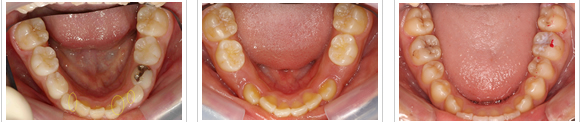

| 下の前歯の裏側は特に歯石が たまりやすい部位です。 |

丁寧なブラッシングと歯石除去で 2ヶ月で症状改善しました。 |